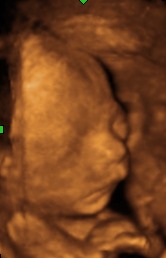

EGY ÚJ ÉLET SZÜLETÉSE